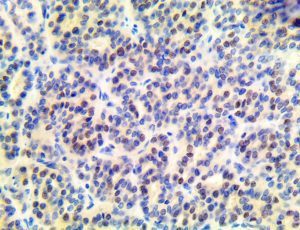

The first cytokines released are interleukin 1β (IL-1β) and tumor necrosis factor-α (TNF-α), which attract a variety of circulating white blood cells (WBCs) to the infection site, including neutrophils, monocytes, macrophages, and natural killer (NK) cells. This response, along with the antipathogenic chemicals released by these cells (i.e., complement), comprise the innate immune response. These cells directly attack the invading pathogen and also release additional cytokines, chief among them interleukin-1 and 6 (IL-6). IL-6 is essential for invoking the adaptive immune response, which calls T-cells, B-cells, and T helper (Th) cells to the infection site. IL-6 also stimulates further recruitment, proliferation and activation of macrophages.

It is the ICU physician who is most likely to witness one of the deadliest manifestations of the abnormal immunological response, the cytokine storm syndrome (CSS). This response is also referred to by some as the cytokine release syndrome (CRS). CSS is characterized by continuous activation and expansion of macrophage and lymphocyte populations, which secrete large amounts of cytokines, causing the cytokine storm. This massive cytokine release is akin to hemophagocytic lymphohistiocytosis (HLH) disease, a syndrome characterized by initial unchecked and persistent activation of cytotoxic T lymphocytes and NK cells.